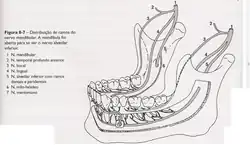

Nervo mandibular

- Nervo bucal: Traz sensibilidade da mucosa e pele da bochecha e gengiva vestibular dos dentes molares inferiores.

- Nervo alveolar inferior e o Nervo lingual: A sensibilidade proveniente da polpa dos dentes de cada lado da mandíbula, bem como das papilas interdentais, periodonto, e tecido ósseo vizinho aos dentes, é transmitida através do nervo alveolar inferior.

- Nervo mentoniano: É formado pela junção das fibras nervosas sensitivas provenientes da pele do mento, da mucosa e pele do lábio inferior e da mucosa e gengiva vestibular dos dentes anteriores. Penetra na mandíbula pelo forame e canal do mesmo nome para contribuir para formação do nervo alveolar inferior.

- Nervo lingual: Origina-se nos dois terços anteriores da língua, mucosa da região sublingual e gengiva lingual de todos os dentes inferiores.